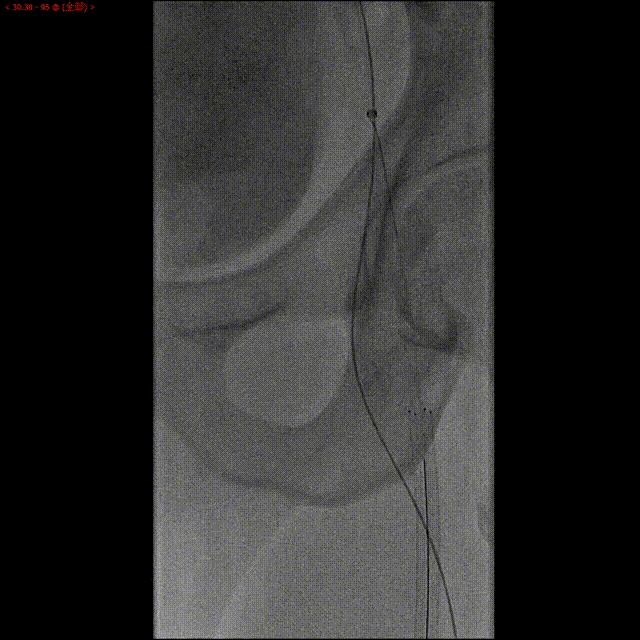

尝试经侧支逆行开通

使用微导管和导丝配合,尝试由股深动脉逆向开通。经尝试,逆向导丝(UB3)通过闭塞段,由于正向通道较小,未能与正向导丝进入同一微通道实现交汇。逆向微导管通过闭塞处困难。

经激光消蚀后,通过导丝导管配合,逆向导丝轻松通过闭塞段。

逆向导丝到达股浅动脉近段,进入正向套鞘,导丝体外化,建立轨道。